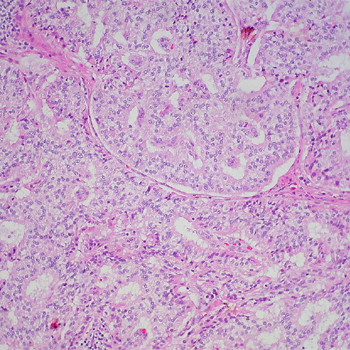

La alteración de las enzimas implicadas en la respiración celular está relacionada con el desarrollo de feocromocitomas y paragangliomas. Las mutaciones de los genes implicados en este proceso provocan una alteración global en la metilación del ADN y la consiguiente alteración de la expresión génica. Los responsables del trabajo han identificado dos nuevos genes vinculados a la aparición de estos tumores.